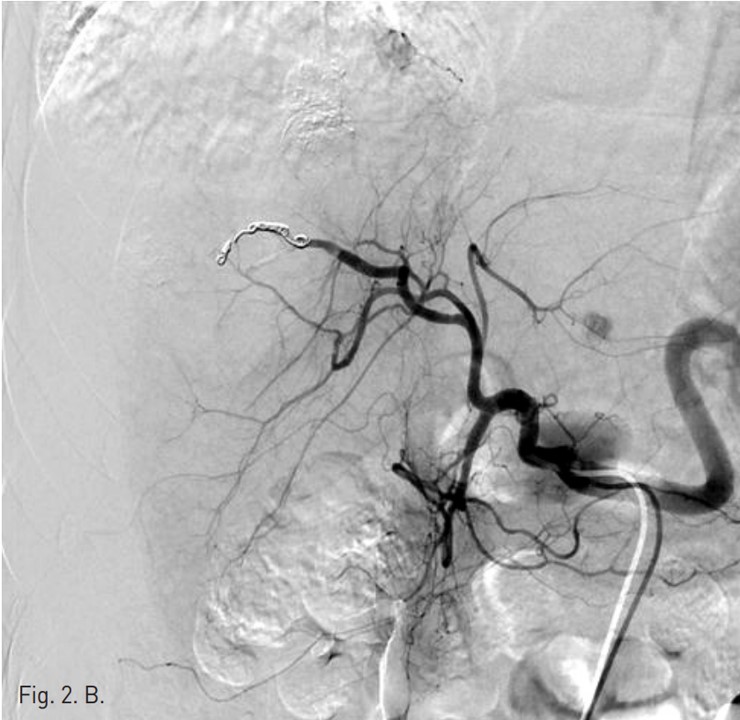

동맥기 간 CT 횡단면 영상에서 간우엽에 두 개의 간암의 크기가 증가되어 고주파 열치료를 시행하였다. 시술후 추적 CT에서 간우엽의 표면을 따라 조영제가 혈관 밖으로 흐르는 것이 발견되었고, 출혈성 복수의 양이 증가되었다 (Fig. 1).

Fig. 1. B

Fig. 1. Dynamic liver CT arterial (A) and portal (B) phase scans show extravasation (arrows) of contrast materials at the surface of the liver and hemoperitoneum around the liver. The focus of extravasation was not clear.